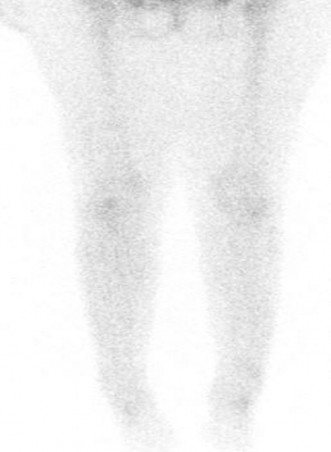

A fluoroscopic image demonstrating the correct placement of an iliosacral screw (S1) traversing the sacral ala and body. Note the careful trajectory to avoid neural structures.